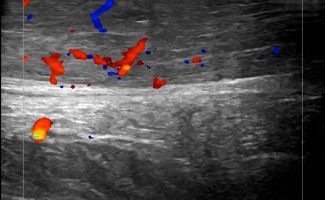

Foot Tendons

Foot Ultrasound allows the diagnosis of tendonitis, tenosynovitis, and rupture in the following tendons:

- Achilles Tendon

- Peroneal Tendons

- Flexor Tendons

- Extensor Tendons